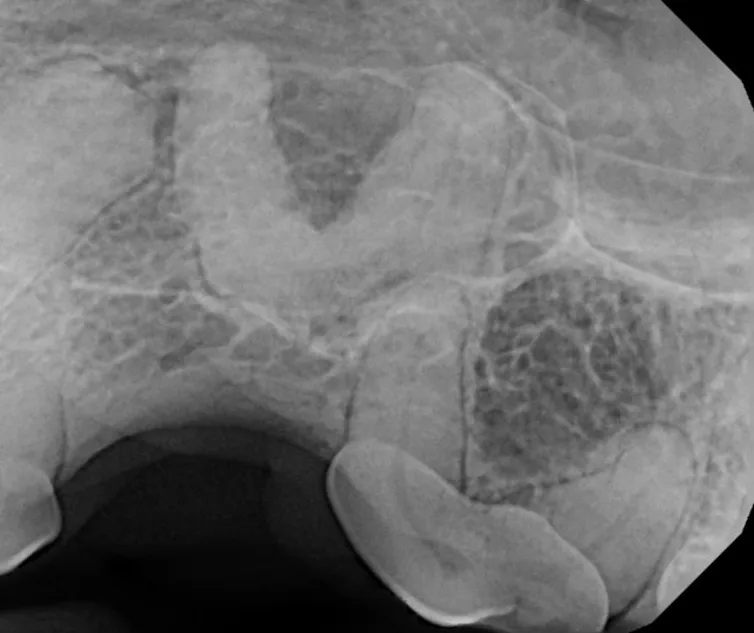

Cone Beam Computed Tomography

The Center now provides advanced imaging via cone beam CT. Cone beam CT is excellent for visualization of bony structures of the skull, nasal cavity, teeth, and ears. Cone beam CT is especially helpful for diagnosing dental disease and evaluation of jaw fractures. It can also be useful for evaluating the sinuses and tympanic bulla. Cone beam CT can be used in conjunction with nasal biopsy and culture to evaluate nasal discharge whether chronic or acute.

Repair of Maxillofacial Fracture

Pets can be involved in trauma that can cause fractures to their head, teeth, and jaw bones. Correctly repairing these fractures is extremely important for your pet to have normal function of their mouth. If a jaw fracture is allowed to heal in an abnormal position, your pet may have great difficulty chewing and can be in significant pain. Many fractures can be successfully treated with minimally invasive oral procedures, but more complicated cases may require bone plating techniques. The Center offers cone beam CT imaging which provides extremely detailed images of the bones of the head and skull. Advanced imaging with CBCT facilitates selection of the best surgical technique to get your pet back to eating and comfort as soon as possible.